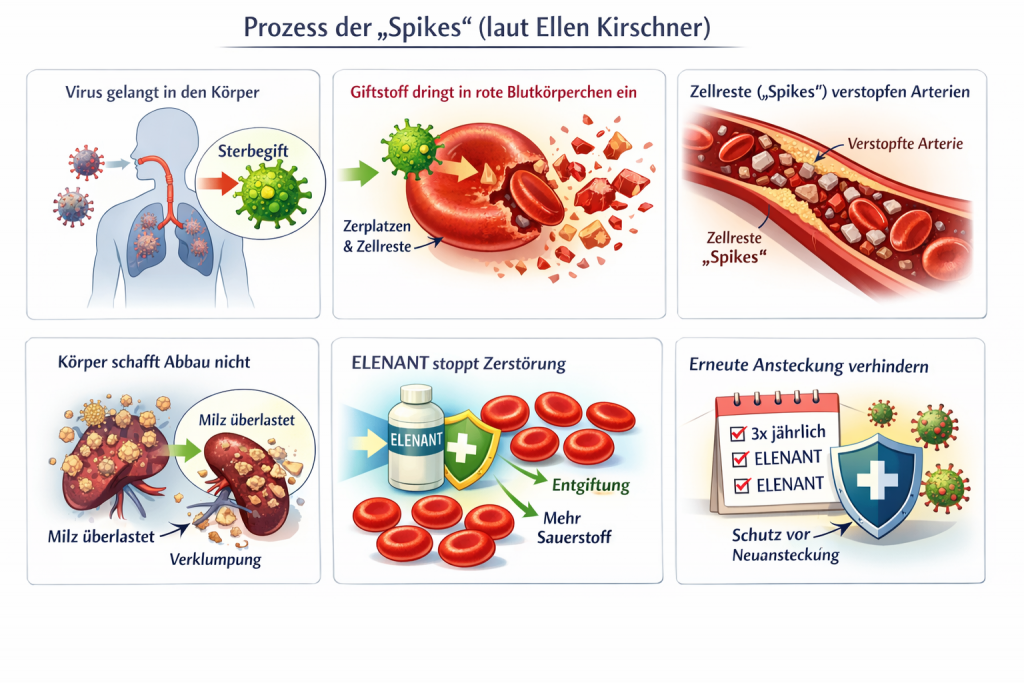

Prozess der „Spikes“

Entstehung der Problematik

- Wenn das Corona-Virus (oder der Impfstoff) in den Körper gelangt, stirbt das Virus nach wenigen Tagen ab.

- Beim Absterben entsteht laut Aussage ein sogenanntes „Sterbegift“.

- Dieser Giftstoff dringt in die roten Blutkörperchen ein.

- Die roten Blutkörperchen zerplatzen und sterben ab.

Bildung der sogenannten „Spikes“

- Durch das Zerplatzen entstehen Zellreste: Zellmembran, Zellkern, Mitochondrien

- Diese toten, linearen Zellreste werden als „Spikes“ bezeichnet.

- Diese Zellreste führen gemäß medizinisch-wissenschaftlicher Erkenntnisse zur Verstopfung der Arterien

Warum der Körper die Spikes nicht ausreichend abbaut

- Die Zellreste sind grundsätzlich körpereigenes Material.

- Normalerweise würden diese vom Körper (insbesondere durch die Milz) natürlich abgebaut.

- Das Problem entsteht laut Darstellung dadurch, dass:

- Die Anzahl der zerstörten roten Blutkörperchen zu hoch ist.

- Der Körper mit dem Abbau nicht nachkommt.

- Die Zellreste sich verklumpen und Ablagerungen bilden.

Rolle von ELENANT®

- ELENANT ® soll die Balance im Energiehaushalt wiederherstellen.

- Es soll zur normalen Bildung roter Blutkörperchen beitragen.

- Der Körper kann neue sauerstoffhaltige rote Blutkörperchen bilden.

- Mehr rote Blutkörperchen führen zu:

- Mehr Blutvolumen

- Mehr Sauerstoffversorgung im Körper

- Laut Darstellung sind nach 3–14 Tagen alle „Spikes“ im Körper abgebaut.

Wiederauftreten der Problematik

- Eine erneute Spike-Vermehrung kann laut Darstellung nur durch eine neue Ansteckung von außen mit dem Virus beginnen.

- Daher wird empfohlen, ELENANT® dreimal jährlich (Mai, August, November) einzunehmen.